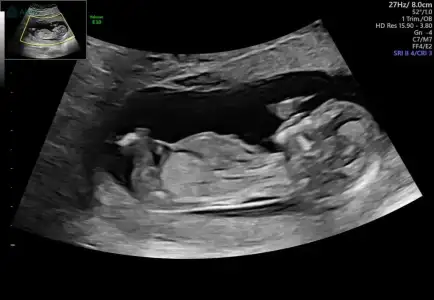

Merhaba kızlar bugün 12+6 olduk bizim minik inatla göstermedi cinsiyetini sonda da iki eliyle bacak arasını kapattı resmen bir sonra ki kontrolüme daha çok var meraktan çatlicam resmen tahminlerinizi alabilir miyim lütfen 😀🌸

Cinsiyeti anlayabiliyor musunuz? Kızımda fetal dna yaptırmıştık. O yüzden cinsiyeti kesindi. Burada henüz karar veremedik. Merak ediyorumm tahmin edebilir misiniz?